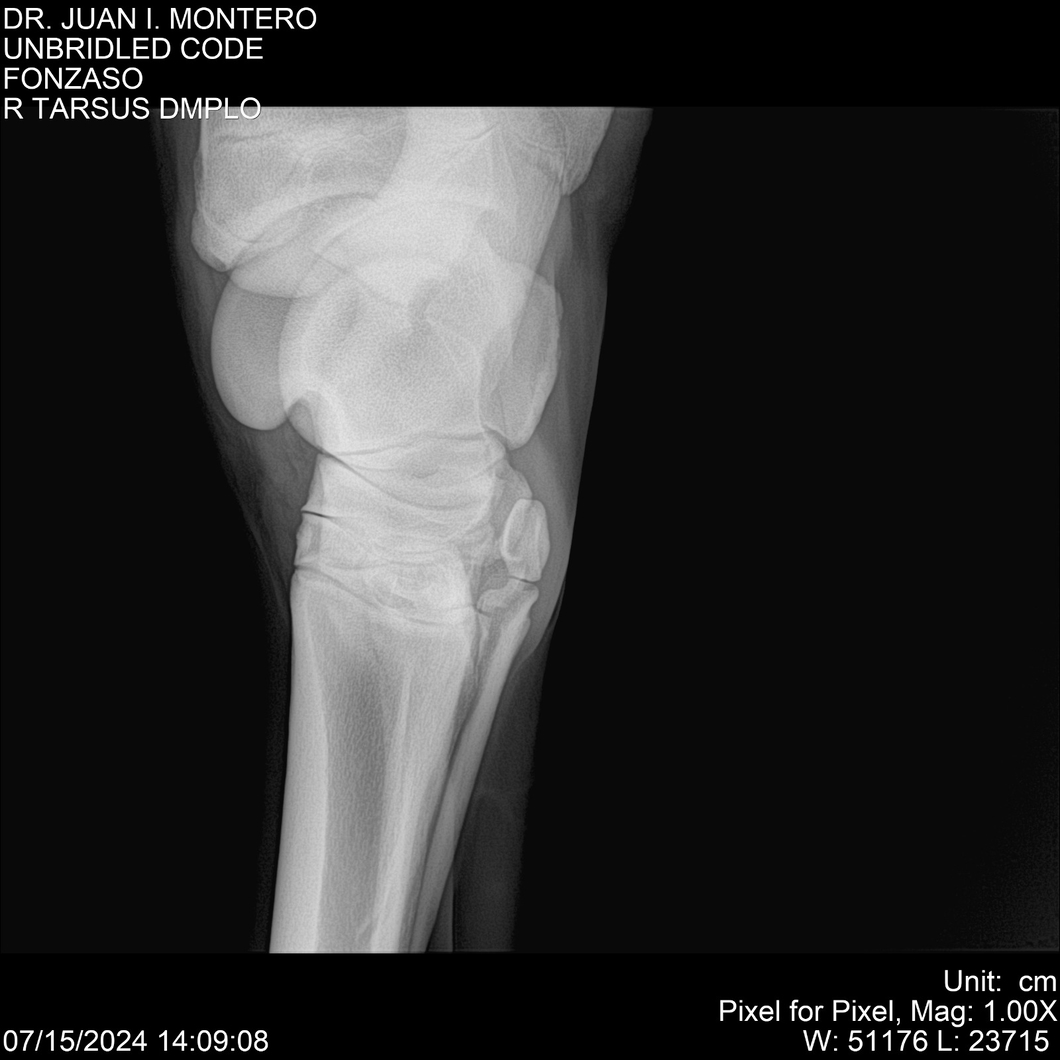

• Empresa: Abelenda N. R., Walter Hugo